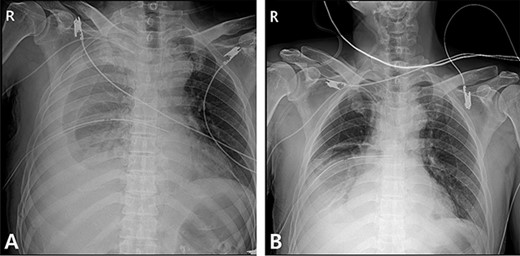

A 59-year-old man was admitted with multiple rib fractures and liver contusion due to a fall injury. He was standing on a chair for working at a farm, and it was knocked over causing him to fall and hit his flank against the corner of the chair. There was continuous pain while resting at the right flank and severe pain with pressure was noted, but no external wounds or bruises were observed. There were right 7th–11th rib fractures, scanty pneumothorax, minimal hemothorax and a 2-cm-sized liver contusion in abdomen and chest computed tomography (CT) scan (Fig. 1A, B). He was hospitalized for pain control and close observation in the general ward, and conservative management was initiated. Also, no significant changes were noted in the following daily follow-up chest radiographs. The patient suddenly complained of right-sided chest and back pain aggravation, cold sweating and fatigue 80 h after the traumatic injury. His mental status was alert, but v/s including systolic blood pressure (SBP) of 100–120 mmHg, heart rate (HR) of 40-60 beats/min and oxygen saturation of 100% during the admission changed to an SBP of 86/60 mmHg, HR of 88 beats/min and oxygen saturation of 97% when the symptoms occurred. Chest radiography was performed after the patient experienced aggravated symptoms, such as right-sided flank pain, cold sweating and fatigue. Compared to the previous scans, signs of increased opacification and peribronchial and parenchymal infiltrations were observed, which were indicative of hemothorax (Fig. 2A, B). We performed enhanced dynamic chest CT to identify any presence of active bleeding. On the chest CT scan, a large amount of hemothorax was identified in the right lung field along with multiple fractures of the right ribs. However, there were no signs of contrast leakage indicative of active bleeding (Fig. 3). Hemoglobin levels decreased from 13.1 g/dl on the day before the symptoms appeared to 11.5 g/dl at the onset of symptoms and to 9.4 g/dl after 2 h. Four packs of RBC transfusion and fluid were administered to the patient, and he was moved to the intensive care unit for close monitoring. And tube thoracostomy was performed, and 1600 ml of fresh blood was drained (Fig. 4A). The following day, 500 ml of blood was drained through the chest tube, but his v/s were stable (Fig. 4B). The amount of bleeding through the chest tube was decreased, but the drained fluid was fresh blood. And we thought that the remaining hematoma was not effectively drained, so the patient’s respiratory discomfort could persist and cause uneffective ventilation. And then we consulted with the Department of Thoracic Surgery, and video-assisted thoracoscopic surgery (VATS) exploratory thoracotomy was performed to identify the bleeding source caused by displaced rib and evacuate the large amount of hematoma. There was a large volume of hematoma within the pleural space and between the right lower lobe, diaphragm and fissure, but no active bleeding point was located. The fractured right 10th rib pierced through the pleural space and was displaced to the thoracic cavity, which was easily reduced. There was no injury surrounding the diaphragm, and although the general lung and chest wall contusions were severe, there were no signs of lung parenchymal lacerations (Fig. 5A–C). Chest tube drainage was serous, and there was no further bleeding. There were no signs of bleeding or any other abnormal findings on chest CT performed at the outpatient clinic, and the patient had no complaints of any symptoms (Fig. 6A, B).

Radiography and CT scan findings. (A) Immediate postoperative chest radiography. (B) A month after surgery, outpatient chestCT.